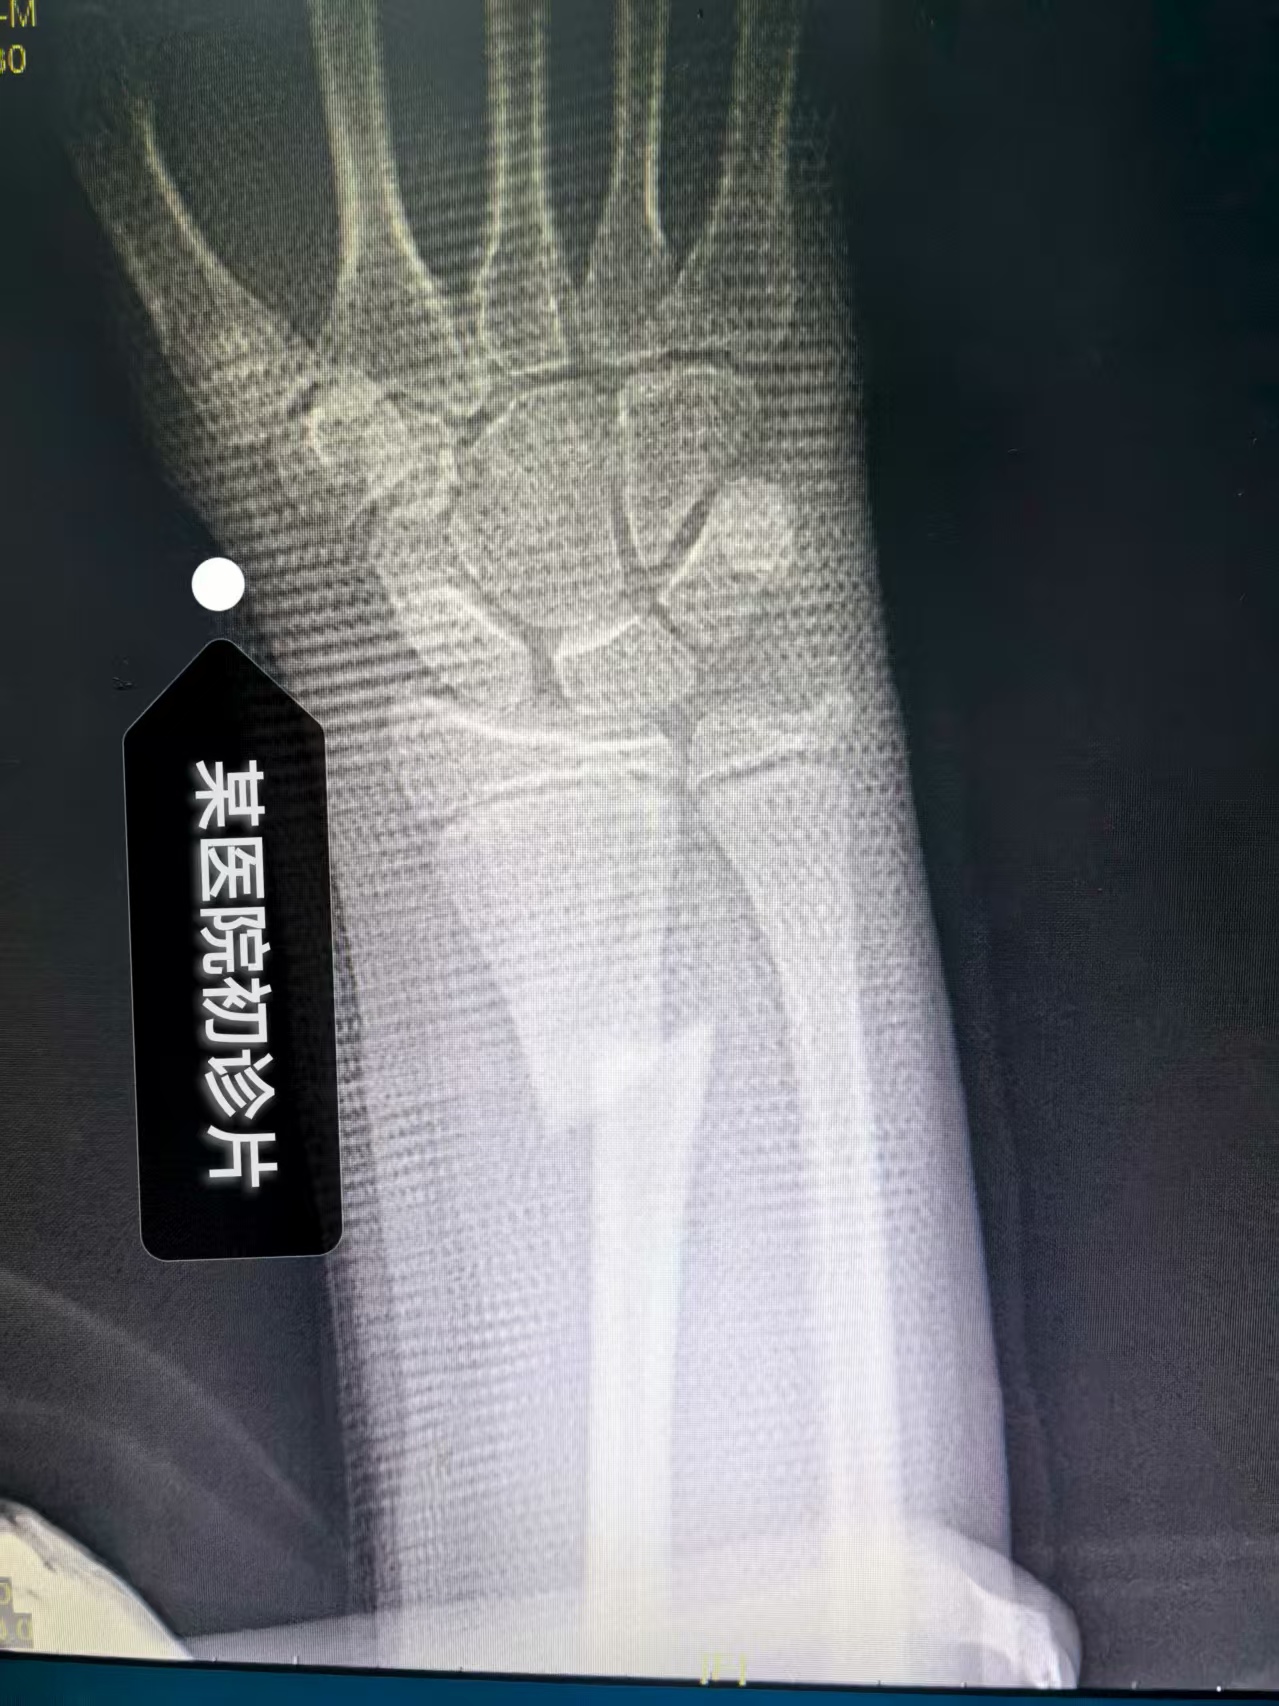

(上面二图,是患者在某大医院初诊,经复位加石膏外固定后,建议手术前照片)